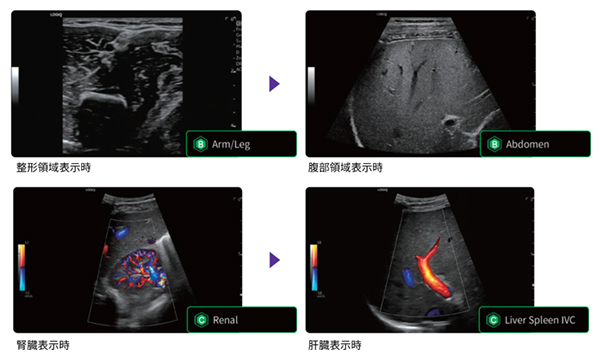

画像を解析した結果から,検査部位に適切な画質設定に切り替える機能や臓器に合わせて適切な血流設定を表示する機能を搭載し,検査の効率化に寄与する。ルーチン検査に使用する時間を短縮し,より時間をかけなければならない症例に注力できるよう,検査の効率化・検査時の負担低減を実現する。